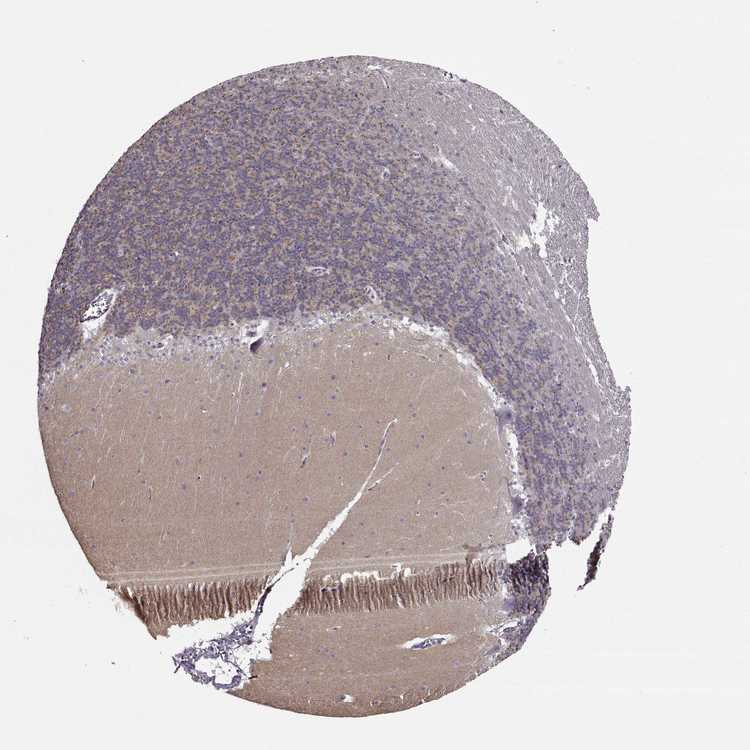

CEREBELLUM - Antibody stainingi

Antibody staining in the annotated cell types in the current human tissue is reported as not detected, low, medium, or high, based on conventional immunohistochemistry profiling in selected tissues. This score is based on the combination of the staining intensity and fraction of stained cells.

Each image is clickable and will lead to virtual microscopy that enables deeper exploration of all samples and also displays staining intensity scores, fraction scores and subcellular localization as well as patient and tissue information for each sample.

Antibody HPA005459Antibody CAB010877

Molecular layer - neuropil Low-

Processes in granular layer Medium-